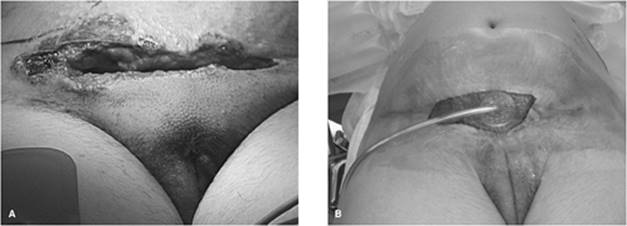

Figure 107.8. A–C: Meleney's synergistic gangrene in a 45-year-old pipe layer who noticed initially a wheal and subsequently required incision and drainage for beta-hemolytic streptococcus.

b. Type II (group A streptococcal) (Figs. 107.8A–C and 107.9A,B): Also known familiarly as ‘flesh-eating bacteria’ or as Meleney's synergistic gangrene. As with type I, a nearly normal appearing overlying skin may result in a delay in diagnosing the underlying ongoing necrosis. A simple incision into the region affected can demonstrate drainage or even gas in advanced cases. Other predisposing factors include varicella infection and the use of nonsteroidal anti-inflammatory drugs (NSAIDs) (18). NSAID use is seen as an immunomodulator, which may predispose to this condition. With type II there is an association with the streptococcal toxic shock syndrome, similar to its staphylococcal counterpart except for the presence of necrosis as the precipitant event.

000960

Figure 107.9. A,B: A 25-year-old female who had a c-section 1 week prior for placenta previa and accreta who 48 hours later developed these purplish minimally raised lesions that grew out beta-hemolytic streptococcus.

Figure 107.13. A-C: Fournier's gangrene involving the perineum but sparing the penis and testicles. Wide debridement has been performed.

Although wide local debridement may be the classical therapy for cases of necrotizing soft tissue infections (Table 107.5), initially, diagnostic surgical exploration can be limited (26,27). A series of small incisions under local anesthesia can be performed to delineate the extent and presence of muscle or facial necrosis. In addition, frozen sections of tissue specimens obtained can establish the diagnosis. However, once the diagnosis is confirmed, there exists no role for conservative debridement or incision and drainage. In the case of Fournier's gangrene, an understanding of the anatomic relationship between the perineum and abdominal wall is important. Below the area of the inguinal ligament, Scarpa's fascia blends into the Colles's fascia, which is contiguous with the dartos fascia of the penis and scrotum (Fig. 107.13A–C). This allows a potential space to exist between the Scarpa's fascia and abdominal oblique musculature, contributing to a potential spread from the perineum to the anterior abdominal wall. Due to Buck's fascia, a deep fascia that covers the corpora and anterior urethra, and due to the retroperitoneal blood supply to the testis, the penis and testicles may be spared.

The two most common pitfalls with a necrotizing soft tissue infection are diagnostic delay and inadequate debridement. Excision of nonviable areas should be early and aggressive, with repeat debridements performed until the local process has been controlled. The use of electrocautery will aid in reducing the considerable operative blood loss if the area of involvement is extensive. With perineal involvement, fecal diversion via colostomy allows for less contamination of the wound site. With urogenital involvement, continued use of a urethral catheter is safe; occasionally suprapubic cystostomy will be necessary. In the case of Fournier's gangrene, the testicles are usually spared. To prevent dessication they are usually placed in a surgically made subcutaneous pocket. If not viable, orchiectomy is performed. In all cases of NF, vacuum-assisted closure devices have shown great promise in decreasing time to grafting and closure of the debrided area (Fig. 107.9B).